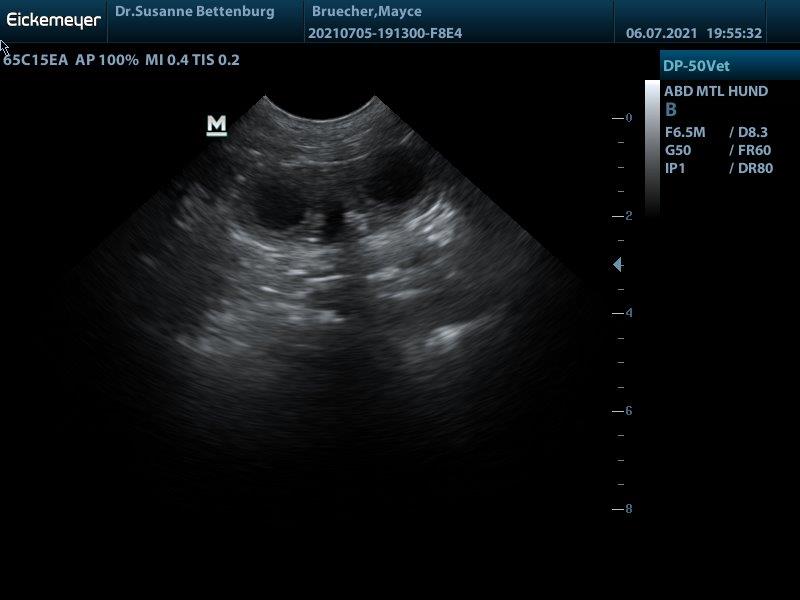

Hurra Mayce ist tragend!!! sodass die Welpen mitte August geboren werden

F-Wurf Mayce wurde am 14.06.2021 von Theo gedeckt. In dem Wurf erwarte ich braune und schwarze Welpen